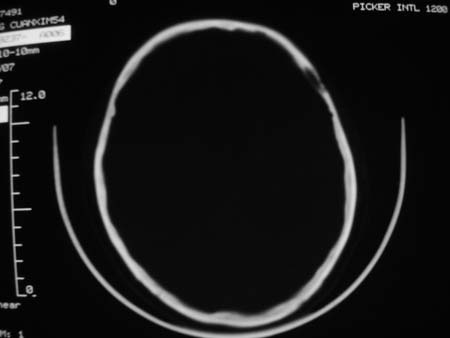

男,54岁,十天前被钢管打伤头顶部,现自述头部不适,视物模糊,并于两天前发觉右枕部有包块,既往未有明显异常.

颅骨多处骨质不完整,内板变薄,右侧额颞部局部呈“穿凿样”骨质缺损,相应区硬膜外密度略增高。多考虑:骨嗜酸性肉芽肿!

颅骨多处骨质不完整,内板变薄,右侧额颞部局部呈“穿凿样”骨质缺损,相应区硬膜外密度略增高。多考虑:骨髓瘤或骨嗜酸性肉芽肿!

颅骨多处骨质不完整,内板变薄,右侧额颞部局部呈“穿凿样”骨质缺损,缺损骨质边缘锐利无硬化,相应区硬膜外密度略增高。多考虑:骨嗜酸性肉芽肿!

颅骨多处骨质不完整,内板变薄,右侧额颞部局部呈“穿凿样”骨质缺损,相应区硬膜外密度略增高。多考虑:骨髓瘤或骨嗜酸性肉芽肿!10天前受伤,不会在2天前才发现头部包块,估计与外伤无关.

骨嗜酸性肉芽肿密度可以这么高么?能不能是脑膜瘤.